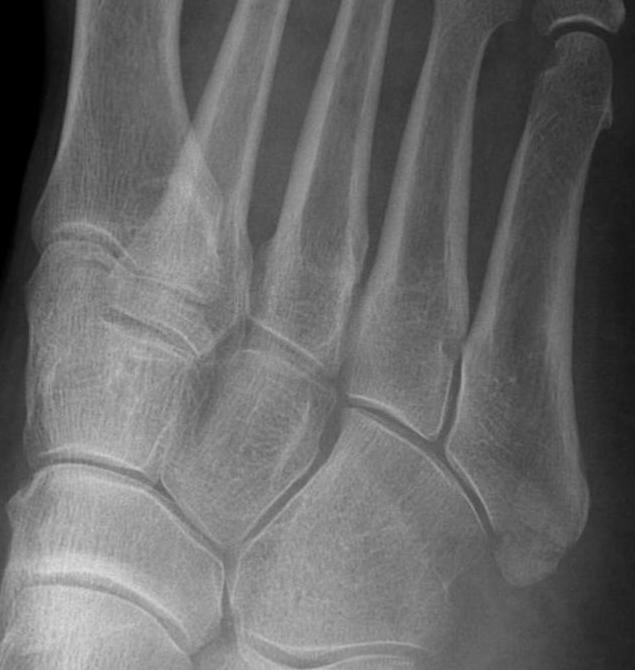

Xray

Zone 2 fractures

Union of zone 2 fracture with nonoperative care

Progression to nonunion of zone 2 fracture with nonoperative care